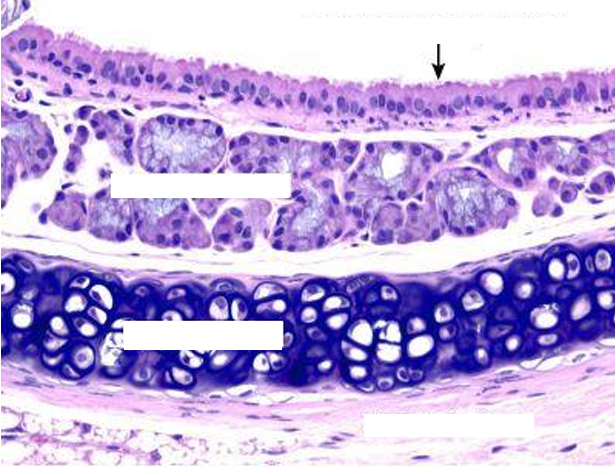

Section in the lung showing intrapulmonary bronchus

Bronchus

Intra pulmonary bronchus

1- epithelium, 2- smooth muscle, 3- cartilage

Intrapulmonary bronchus

1. Epithelium

2. Smooth muscles spirally arranged

3. Plates of hyaline cartilage in adventitia